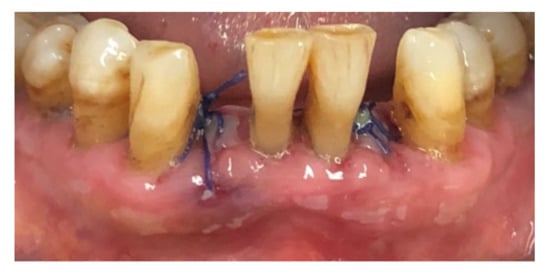

| Tissue colour: | 50% of gingiva red |

| Granulation tissue: | Present | |

| Incision margin: | Not epithelialized, with loss of epithelium beyond incision margin | |

| Suppuration: | Present | |

| Incision margin: | Not epithelialized, with connective tissue exposed | |

| Suppuration: | None | |

| Granulation tissue: | None | |

| Incision margin: | No connective tissue exposed | |

| Tissue colour: | 25% of gingiva red |

| Tissue colour: | All tissues pink |

| Suppuration: | None |